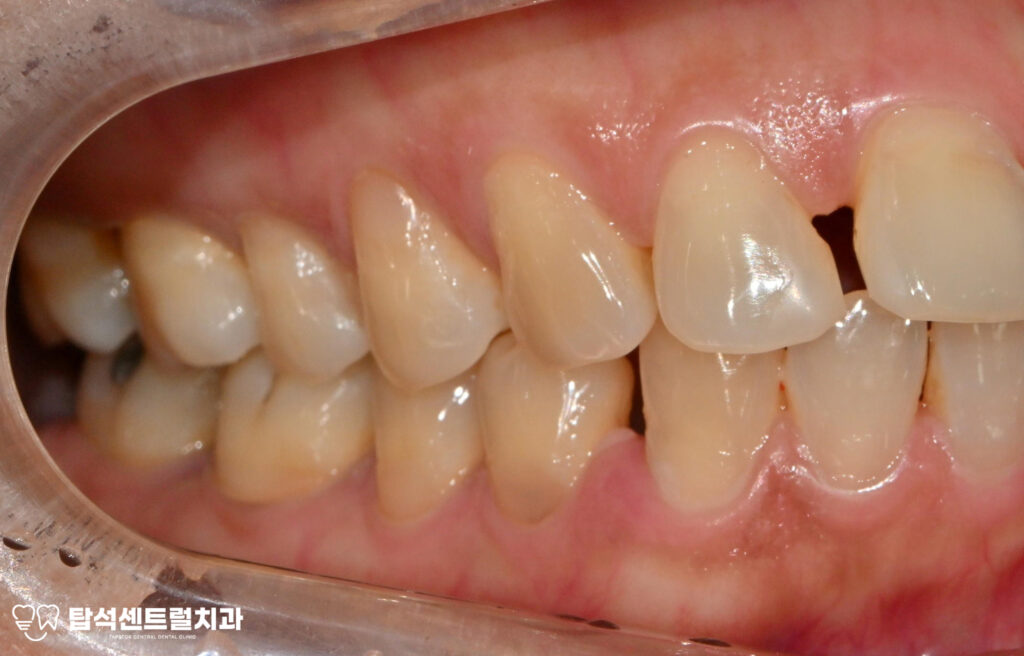

다수 치아에서 나타난 치경부 마모증은

레진으로 수복하는 것이 적절합니다.

치경부 마모증은 치아 목 부분이 닳아서

움푹 파인 상태를 말하며,잘못된 칫솔질이나

이갈이 습관으로 발생합니다.

치경부 마모증 부위도 레진으로 수복하여

전반적인 구강 환경을 개선했습니다.

레진 수복을 통해 자연 치아색과 유사한 재료로

자연스러운 외관을 유지할 수 있었습니다.